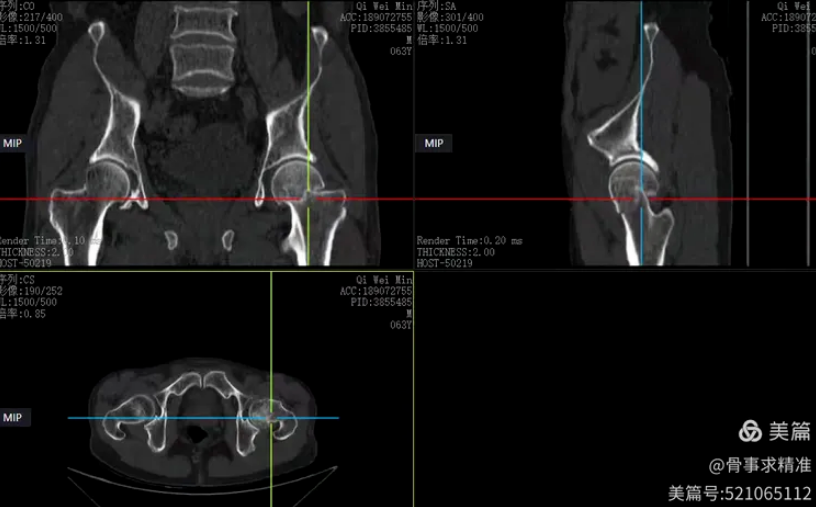

在全髋关节置换中,机器人实现髋臼磨挫深度、角度、臼杯前倾角、外展角完全量化,置钉方向与深度实时可视监测。尤其在DDH发育不良、髋关节翻修等解剖变异复杂病例中,精准导航能够降低手术风险,提高假体稳定性与长期生存率。

髋关节术后片